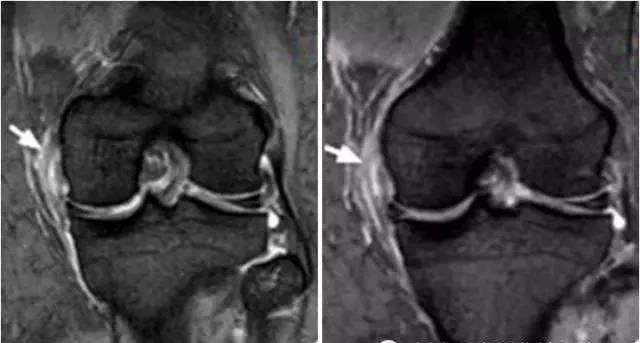

4、桶柄状撕裂

为纵形撕裂伴碎片向内侧移位,这种移位的片段类似于桶的柄,该型撕裂几乎累及半月板的所有部位,常易漏诊,在 MRI 上可以有多种表现,主要为半月板的宽度减小,在通过半月板体部的冠状面上未见到与对侧半月板共同构成的蝶形表现,同时可见到内移的半月板碎片位于髁间窝或交叉韧带旁,可形成双前、后交叉韧带征,这一征象在诊断半月板桶柄状撕裂中有重要意义;